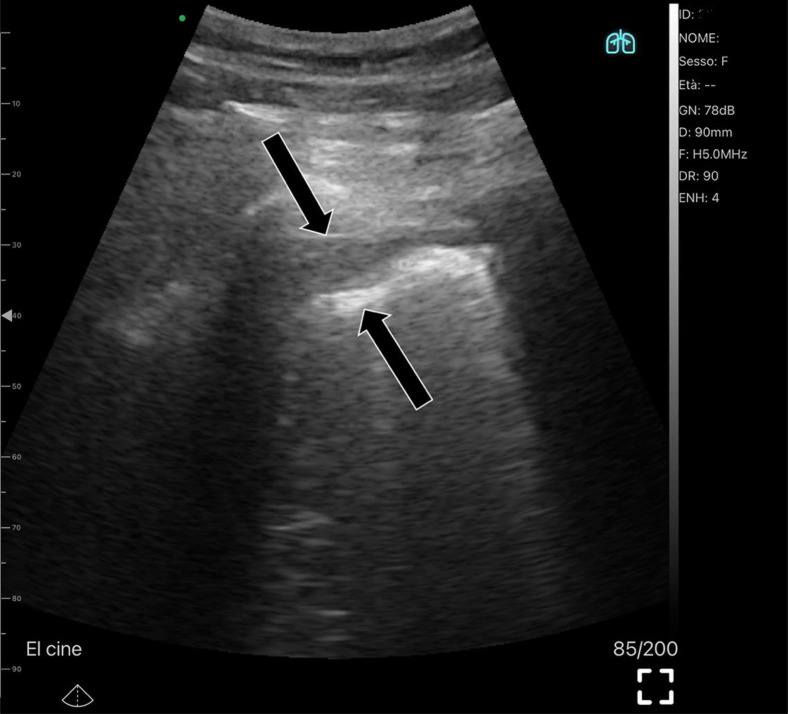

Abstract Image